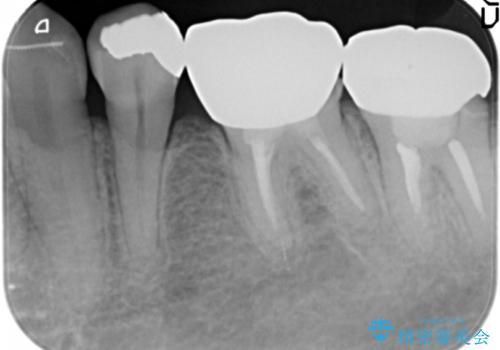

- 低予算で銀歯を白くしたいとご希望し来院された患者様です。

右上小臼歯(右上5)はオールセラミッククラウン(e-max press)、下顎臼歯(下顎両側67)はメタルボンドクラウンによりやりかえることにしました。

再根管治療はご希望されず、行っておりません。

右上小臼歯(右上5):オールセラミッククラウン エコノミー

下顎両側臼歯(下顎両側67):メタルボンドクラウン エコノミー